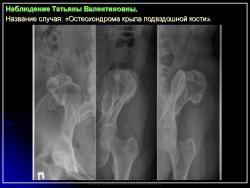

Наблюдение Соколиной И.А. и Зуевой М.А.

Приложения:

1.OHM_.Slayd9_.JPG2.OHM_.Slayd10.JPG3.OHM_.Slayd11.JPG4.OHM_.Slayd12.JPG5.OHM_.Slayd13.JPG